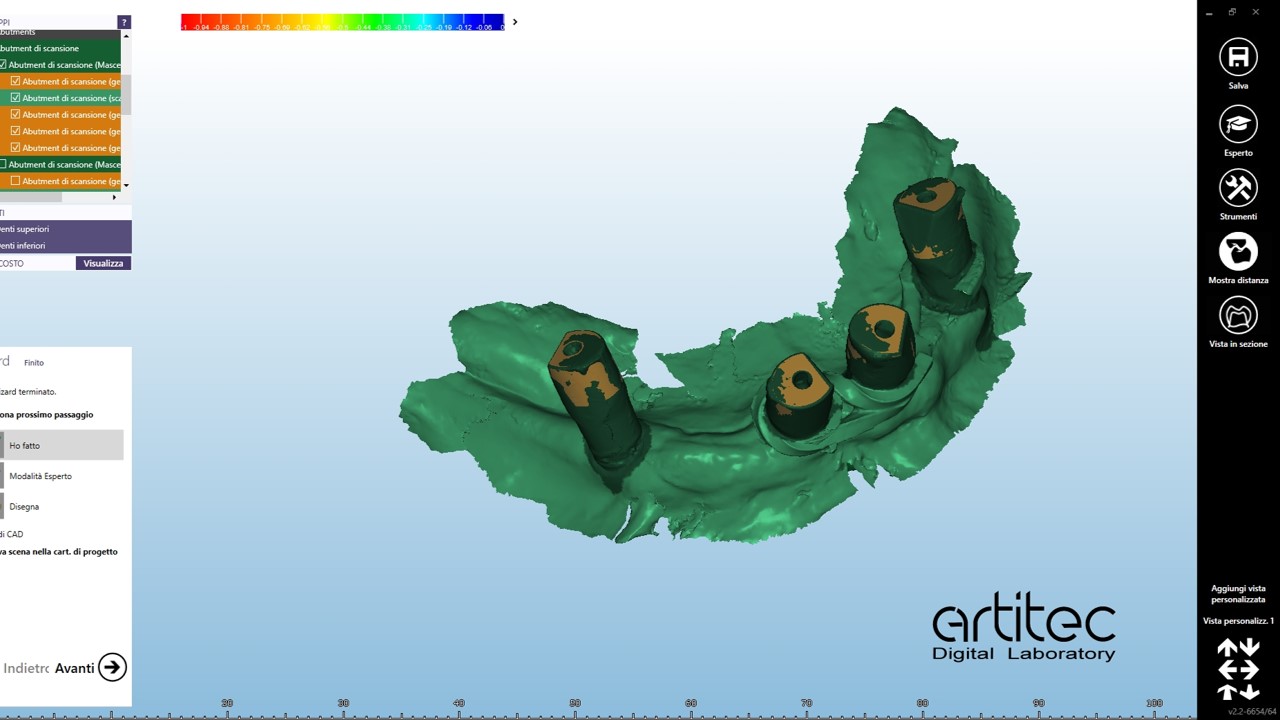

foto 11 scan body inferiore

foto 12 scan body inferiore allineati

foto 13 match tra scansioni e fotografia

foto 14 outline per definire volumi protesici

La fase protesica inizia con la ribasatura delle protesi provvisorie per rilevare la corretta anatomia della cresta. Quindi si procede a scansionare con scansione intraorale le impronte ottenute fuori dal cavo orale, poi le protesi provvisorie ribasate ricollocate nel cavo orale e la loro occlusione. Infine, si scansionano le creste edentule dopo aver posizionato gli scan body per tecnica digitale per rilevare la posizione degli impianti. Per la pianificazione sono scattate delle fotografie intraorali ed extraorali per la definizione dei limiti perimetrali del volto al fine di poter eseguire la programmazione del caso tramite il software di previsualizzazione. Le scansioni così ottenute sono poi inviate al laboratorio per la realizzazione di un prototipo delle protesi in prova.